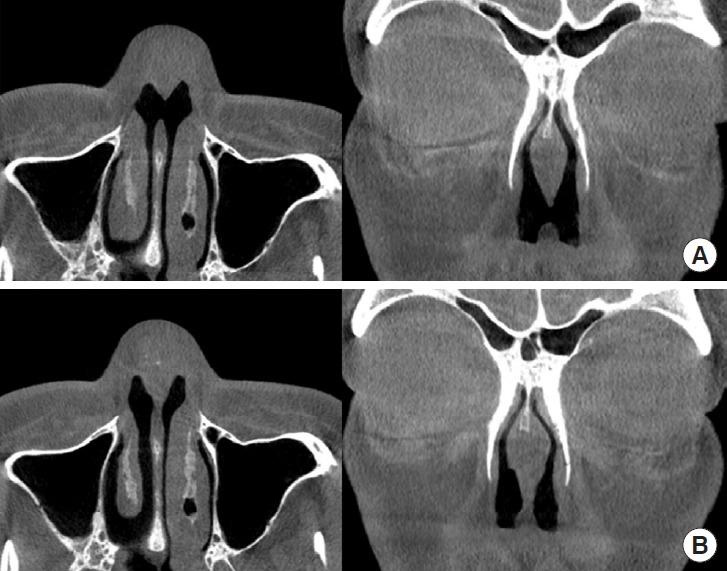

Septal perforation is an anatomical defect of the nasal septum that leads to impaired nasal function, including obstruction and respiratory issues. In this study, a novel surgical approach was introduced to address septal perforations, focusing on the use of costal composite chondro-perichondrial grafts bilaterally in a symmetric manner. This composite graft, composed of costal cartilage and perichondrium, provides mechanical support, aids vascularization, and minimizes perichondrial shrinkage. A case study of a 23-year-old patient with septal perforation resulting from multiple rhinoplasty procedures is presented. The surgical procedure involved the use of a composite graft to close the septal perforation and correct the nasal deformity. The postoperative results demonstrated successful septal perforation closure and relief from nasal discomfort. This study highlights the advantages of this method, particularly its simplicity and straightforward surgical procedures for closing septal perforations of various sizes, and its suitability for rhinoplasty surgeons who are familiar with costal cartilage harvesting.